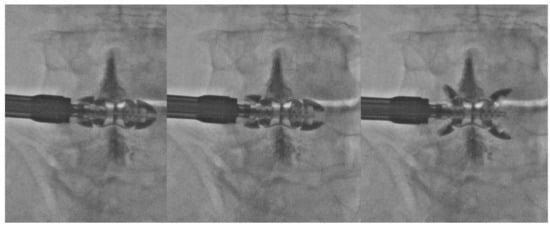

- Bonaldi, G.; Bertolini, G.; Marrocu, A.; Cianfoni, A. Posterior vertebral arch cement augmentation (spinoplasty) to prevent fracture of spinous processes after interspinous spacer implant. AJNR Am. J. Neuroradiol. 2012, 33, 522–528. [Google Scholar] [CrossRef]

- Manfré, L. Posterior Arch Augmentation (Spinoplasty) before and after Single and Double Interspinous Spacer Introduction at the Same Level: Preventing and Treating the Failure? Interv Neuroradiol. 2014, 20, 626–631. [Google Scholar] [CrossRef]